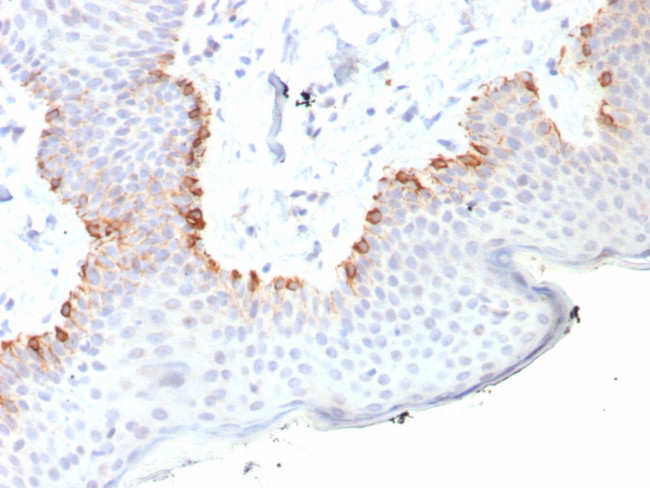

MART-1/Melan-A/MLANA (Melanoma Marker) Antibody in Immunohistochemistry (Paraffin) (IHC (P))

MART-1/Melan-A/MLANA (Melanoma Marker) Antibody (2315-RBM20-P1ABX) in IHC (P)

Formalin-fixed, paraffin-embedded human skin stained with MART-1 Recombinant Rabbit Monoclonal Antibody (MLANA/8108R). HIER: Tris/EDTA, pH9.0, 45 min. 2 °: HRP-polymer, 30 min. DAB, 5 min. {{ $ctrl.currentElement.advancedVerification.fullName }} 验证信息 View more